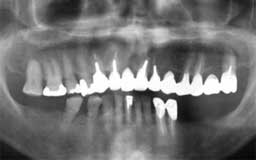

Hさん 初診時 53歳 男性

50歳頃まではもう少し歯があったそうですが、歯科医院に行くたびに「歯槽膿漏です」といわ れて抜歯。60歳まで何とか総入れ歯にしたくないという

Hさん 19年後 72歳

上顎の補綴処置と左下の親知らずを抜歯。歯槽膿漏の手術を行うことなく月に1度の歯石除去 を継続して行った結果、初診時から大きく変化することなく19年を経過しました